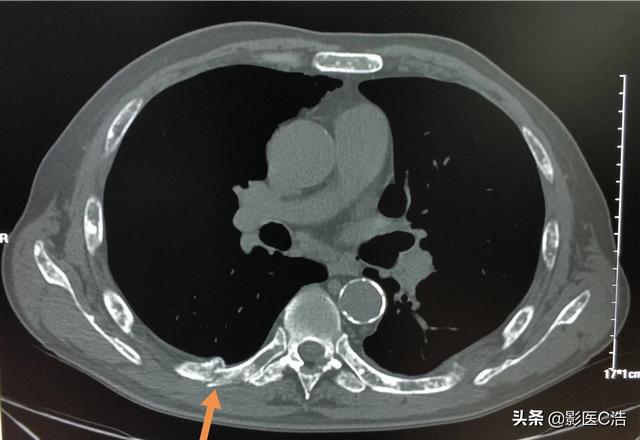

この症例は58歳のゲイ男性で、肩を軽く伸ばしただけで痛みが続くようになり、X線検査で低密度病巣が見つかった:

これは骨転移に基づく軽微な外力による病的骨折であった。穿刺が行われ、病理結果は低分化肺腺癌の骨転移であった。

左肺にあるこの不規則な結節が原発巣で、わずか2.6cmしかない。このような骨転移を伴う肺がんは、もはや手術不可能です。肺がんはあまりにもありふれた病気であり、初期症状の中には非典型的なものや無症状のものさえあるからだ。肺がんの約30%では、転移の症状が最初の症状であり、さらなる肺がんが発見される前に転移が最初に発見される。